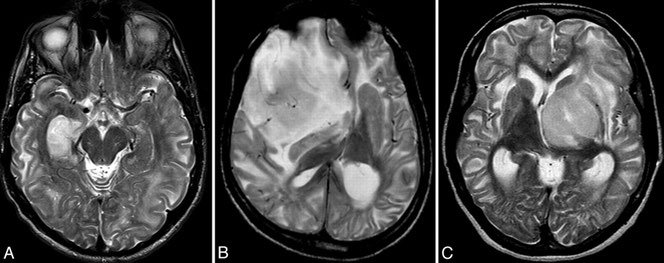

Disturbo neurometabolico caratterizzato da elevati livelli di L2 acido hydroxyglutarico nelle urine, nel plasma e nel liquido cerebrospinale.

Colpisce il sistema nervoso centrale, con segni clinici evidenti di solito tra i 6 e i 12 mesi. I sintomi includono crisi epilettiche, andatura “traballante”, tremori, rigidità muscolare a seguito di esercizio o di eccitazione e comportamento alterato. L2HGA è una malattia trasmessa secondo un meccanismo autosomatico recessivo e questi sono i possibili risultati: